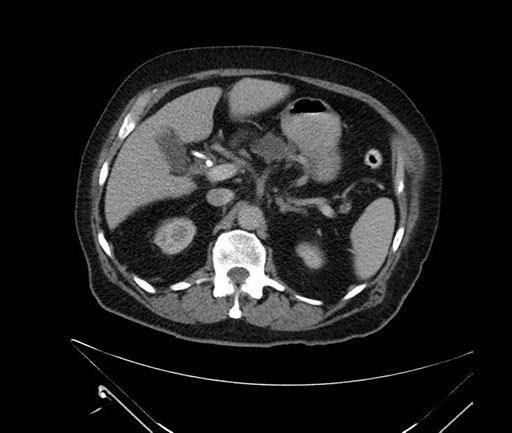

Whipple (pancreaticoduodenectomy) [case 7]

Imaging Analysis

Look through the patient's CT scan to identify any areas of concern for the necessary procedure.

Axial - 3 months prior